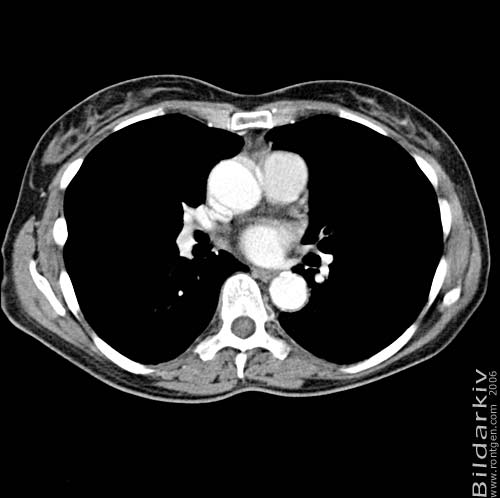

Snitt över thorax med kontrast. Sk. mediastinum-fönstersättning.

Mediastinum